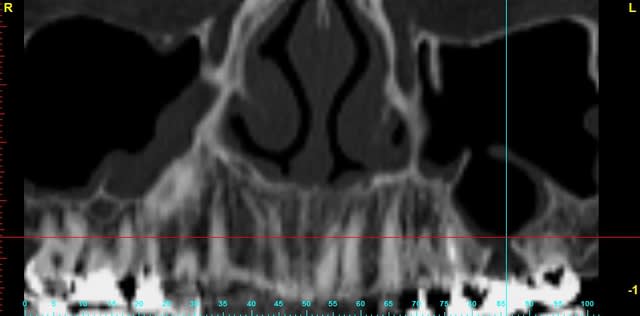

je dois pratiquer un rehaussement de plancher sinusien par volet latéral et je ne sais comment gérer le décollement de la membrane de Schneider au niveau de la communication bucco sinusale

Dès le départ, je m'inquiète au niveau du décollement du lambeau sur la CBS, on risque de déchirer à ce moment là

je joins quelques captures pour vous faire une idée

vos avis éclairés sont les bienvenus